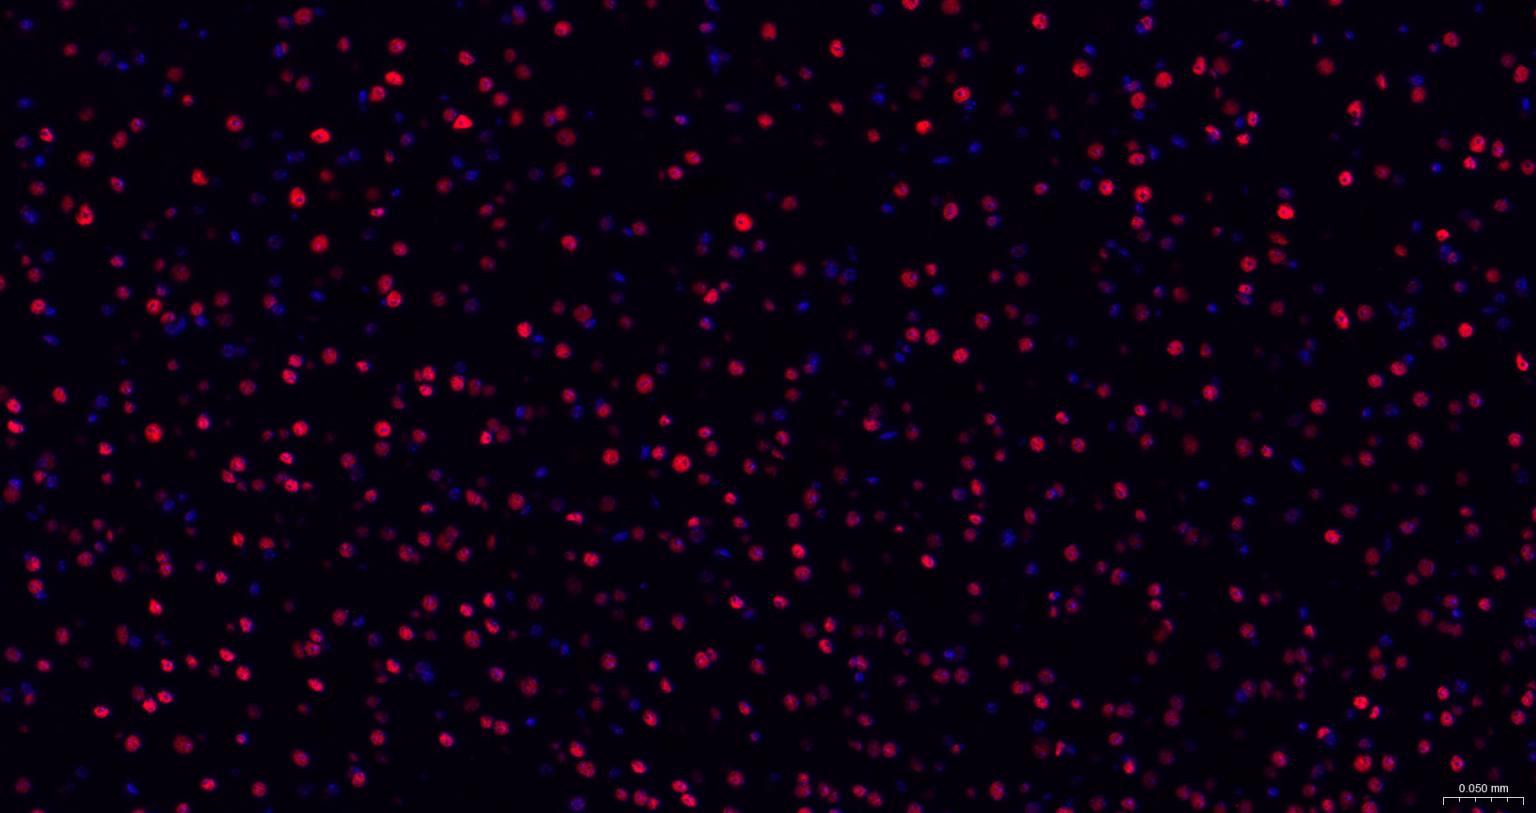

Paraformaldehyde-fixed, paraffin embedded Mouse Cerebrum; Antigen retrieval by boiling in sodium citrate buffer (pH6.0) for 15 min; The section was incubated with TARDBP Monoclonal Antibody, Unconjugated (bsm-52949R) at 1:200 overnight at 4°C. Followed by conjugated Goat Anti-Rabbit IgG antibody (Red, bs-0295G-BF594), DAPI (blue, C02-04002) was used to stain the cell nuclei.